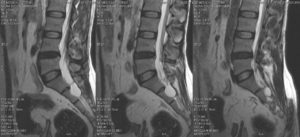

Киста пояснично-крестцового отдела на МРТ